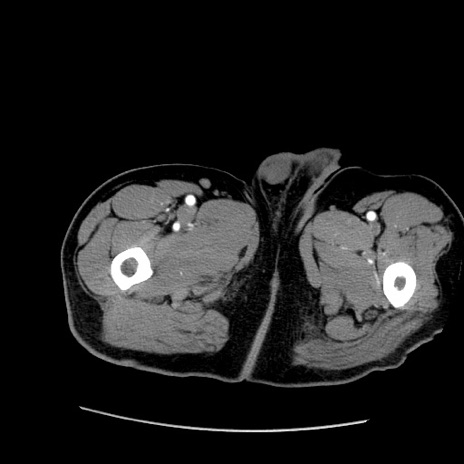

症例22(横断像)

【症例】50歳代男性

【主訴】腹痛

【現病歴】AVMからの被殻出血のため回復期リハ病棟入院中。 本日午後3時頃急に下腹部痛が出現した。

【既往歴】AVM、被殻出血、虫垂炎、高血圧

【身体所見】意識晴明、左半身不全麻痺、会話の理解は良好、36.5°C、腹部:膨隆、全体に板状硬、下腹部正中に圧痛点あり、反跳痛-、筋性防御不明、右下腹部にope scar

【データ】WBC 9400、CRP 0.06